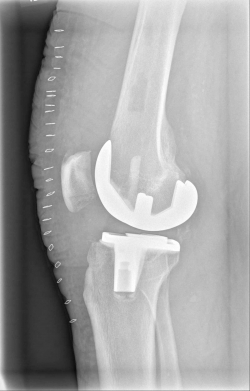

Example X-ray images before and after implantation of a Persona knee prosthesis with robot.

| b) nach Implantation der Knie-Totalendoprothese angefertigte Röntgenaufnahmen | |